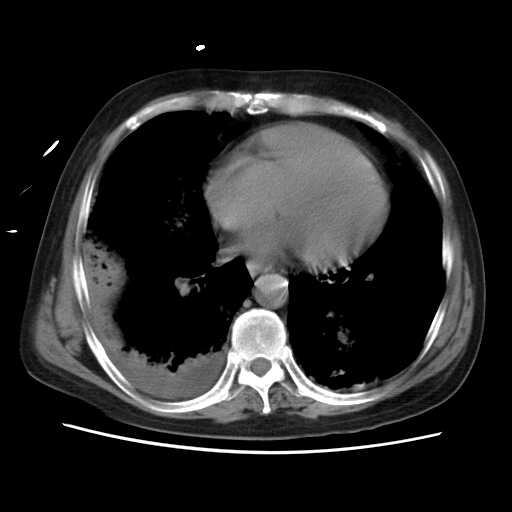

2008.8.17ct定位片

2008.8.17ct